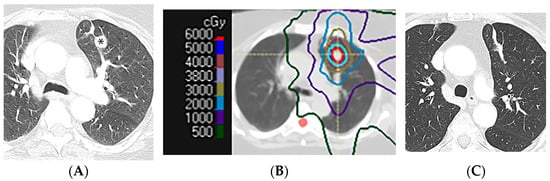

2.2. Three-Dimensional Conformal Radiotherapy

2.3. Intensity-Modulated Radiotherapy